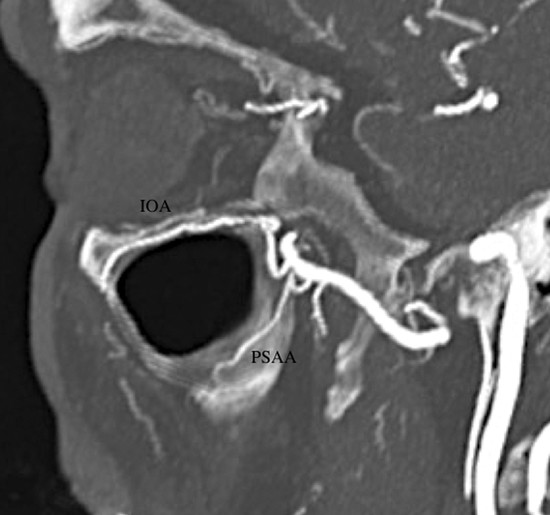

The posterior superior alveolar artery (PSAA) usually represents the first branch of the pterygopalatine segment of the MA. It runs close to the periosteum of the convexity of the maxillary tuberosity and divides into two branches: a lateral descending vessel (dental branch) and an internal vessel (peridental branch). This internal branch perforates the tuberosity of the maxilla and courses endosseously supplying the mucosa of the maxillary sinus and anastomosing with the IOA 2 , 4 , 7 (Fig. 3‑8).